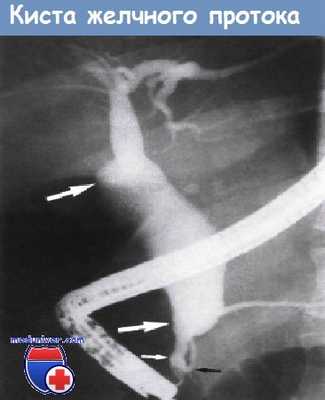

Киста общего желчного протока. Эндоскопическая ретроградная холангиография.

Веретенообразное расширение дистального отдела общего печеночного протока (обозначено большими белыми стрелками) и проксимального и среднего отделов общего желчного протока.

Диаметр дистальной части общего желчного протока (обозначен маленькой белой стрелкой) в норме.

Аномалии протока поджелудочной железы (обозначен черной стрелкой) не выявлено.